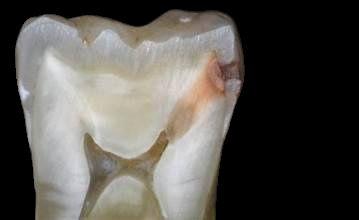

Tooth anatomy & cavities

Bacteria produce acidic byproducts

Acid removes minerals from teeth

• Caries (cavities)

Demineralization/Remineralization